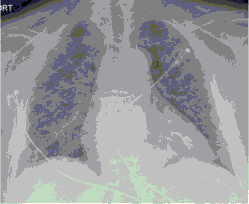

4.3. ЛУЧЕВАЯ ДИАГНОСТИКА COVID-19

Методы лучевой диагностики применяют для выявления COVID-19 пневмоний, их осложнений, дифференциальной диагностики с другими заболеваниями легких, а также для определения степени выраженности и динамики изменений, оценки эффективности проводимой терапии.

Стандартная РГ имеет низкую чувствительность в выявлении начальных изменений в первые дни заболевания и не может применяться для ранней диагностики. Информативность РГ повышается с увеличением длительности течения пневмонии. Рентгенография с использованием передвижных (палатных) аппаратов является основным методом лучевой диагностики патологии ОГК в ОРИТ. Применение передвижного (палатного) аппарата оправдано и для проведения обычных РГ исследований в рентгеновском кабинете. В стационарных условиях относительным преимуществом РГ в сравнении с КТ являются большая пропускная способность. Метод позволяет уверенно выявлять тяжелые формы пневмоний и отек легких различной природы, которые требуют госпитализации, в том числе направления в ОРИТ.

КТ имеет высокую чувствительность в выявлении изменений в легких, характерных для COVID-19. Применение КТ целесообразно для первичной оценки состояния ОГК у пациентов с тяжелыми прогрессирующими формами заболевания, а также для дифференциальной диагностики выявленных изменений и оценки динамики процесса. КТ позволяет выявить характерные изменения в легких у пациентов с COVID-19 еще до появления положительных лабораторных тестов на инфекцию с помощью МАНК. В то же время, КТ выявляет изменения легких у значительного числа пациентов с бессимптомной и легкой формами заболевания, которым не требуется госпитализация. Результаты КТ в этих случаях не влияют на тактику лечения и прогноз заболевания при наличии лабораторного подтверждения COVID-19. Поэтому массовое применение КТ для скрининга асимптомных и легких форм болезни не рекомендуется. При первичном обращении пациента с подозрением на COVID-19 рекомендуется назначать КТ только при наличии клинических и инструментальных признаков дыхательной недостаточности (SpO2 < 95%, ЧДД > 22).

4. Все выявляемые при лучевых исследованиях признаки, включая КТ-симптомы, не являются специфичными для какого-либо вида инфекции и не позволяют установить этиологический диагноз. Вне клинической (эпидемической) ситуации они не позволяют отнести выявленные изменения к пневмонии COVID-19 и дифференцировать их с другими пневмониями и невоспалительными заболеваниями. Данные лучевого исследования не заменяют результаты обследования на РНК SARS-CoV-2. Отсутствие изменений при КТ не исключает наличие COVID-19 и возможность развития пневмонии после проведения исследования.

5. Рекомендовано проведение лучевого исследования пациентам при среднетяжелом, тяжелом и крайне тяжелом течении ОРИ с целью медицинской сортировки, оценки характера изменений в грудной полости и определения прогноза заболевания:

- выполнение КТ легких без внутривенного контрастирования в стационарных условиях или в амбулаторных - при показаниях к госпитализации;

- выполнение РГ легких в двух проекциях, если проведение КТ в данной медицинской организации/клинической ситуации невозможно.